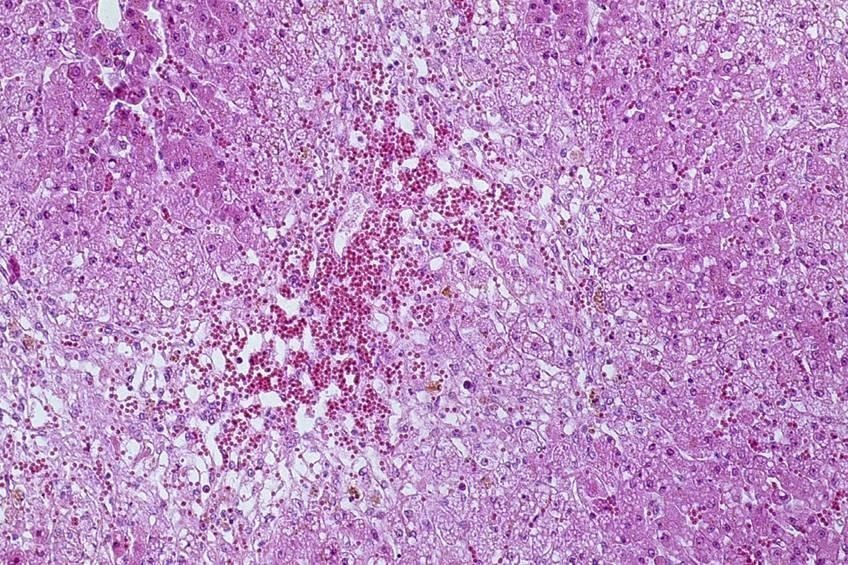

Describe this lesion.

Name a possible sequelae

The parenchyma of the liver shows disseminated round black lesions with non-affected tissue showing either redenning or multifocally shown to be pale tan. The surface of the liver is diffusely roughened.

Chronic disseminated severe fibrosing passive hyperaemia of the liver

Sequelae: acquired porto-systemic shunt

Chronic fibrosis of the liver leading to reduced and inadequate liver function.